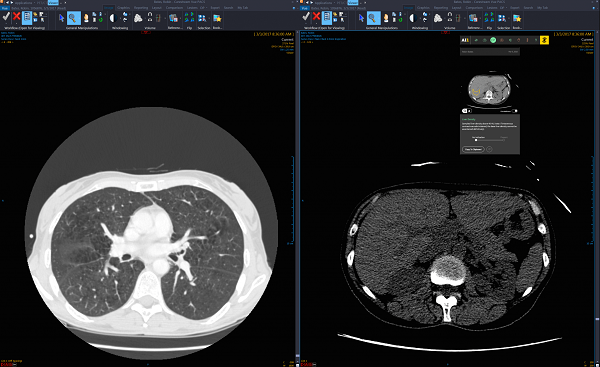

Công ty Zebra Medical Vision sử dụng các thuật toán dựa trên AI để tìm ra các vùng xuất huyết não

• Zebra Medical Vision - 50 triệu USD – Sử dụng công nghệ trí tuệ nhân tạo giúp các bác sĩ chẩn đoán hình ảnh X quang giảm khối lượng công việc.